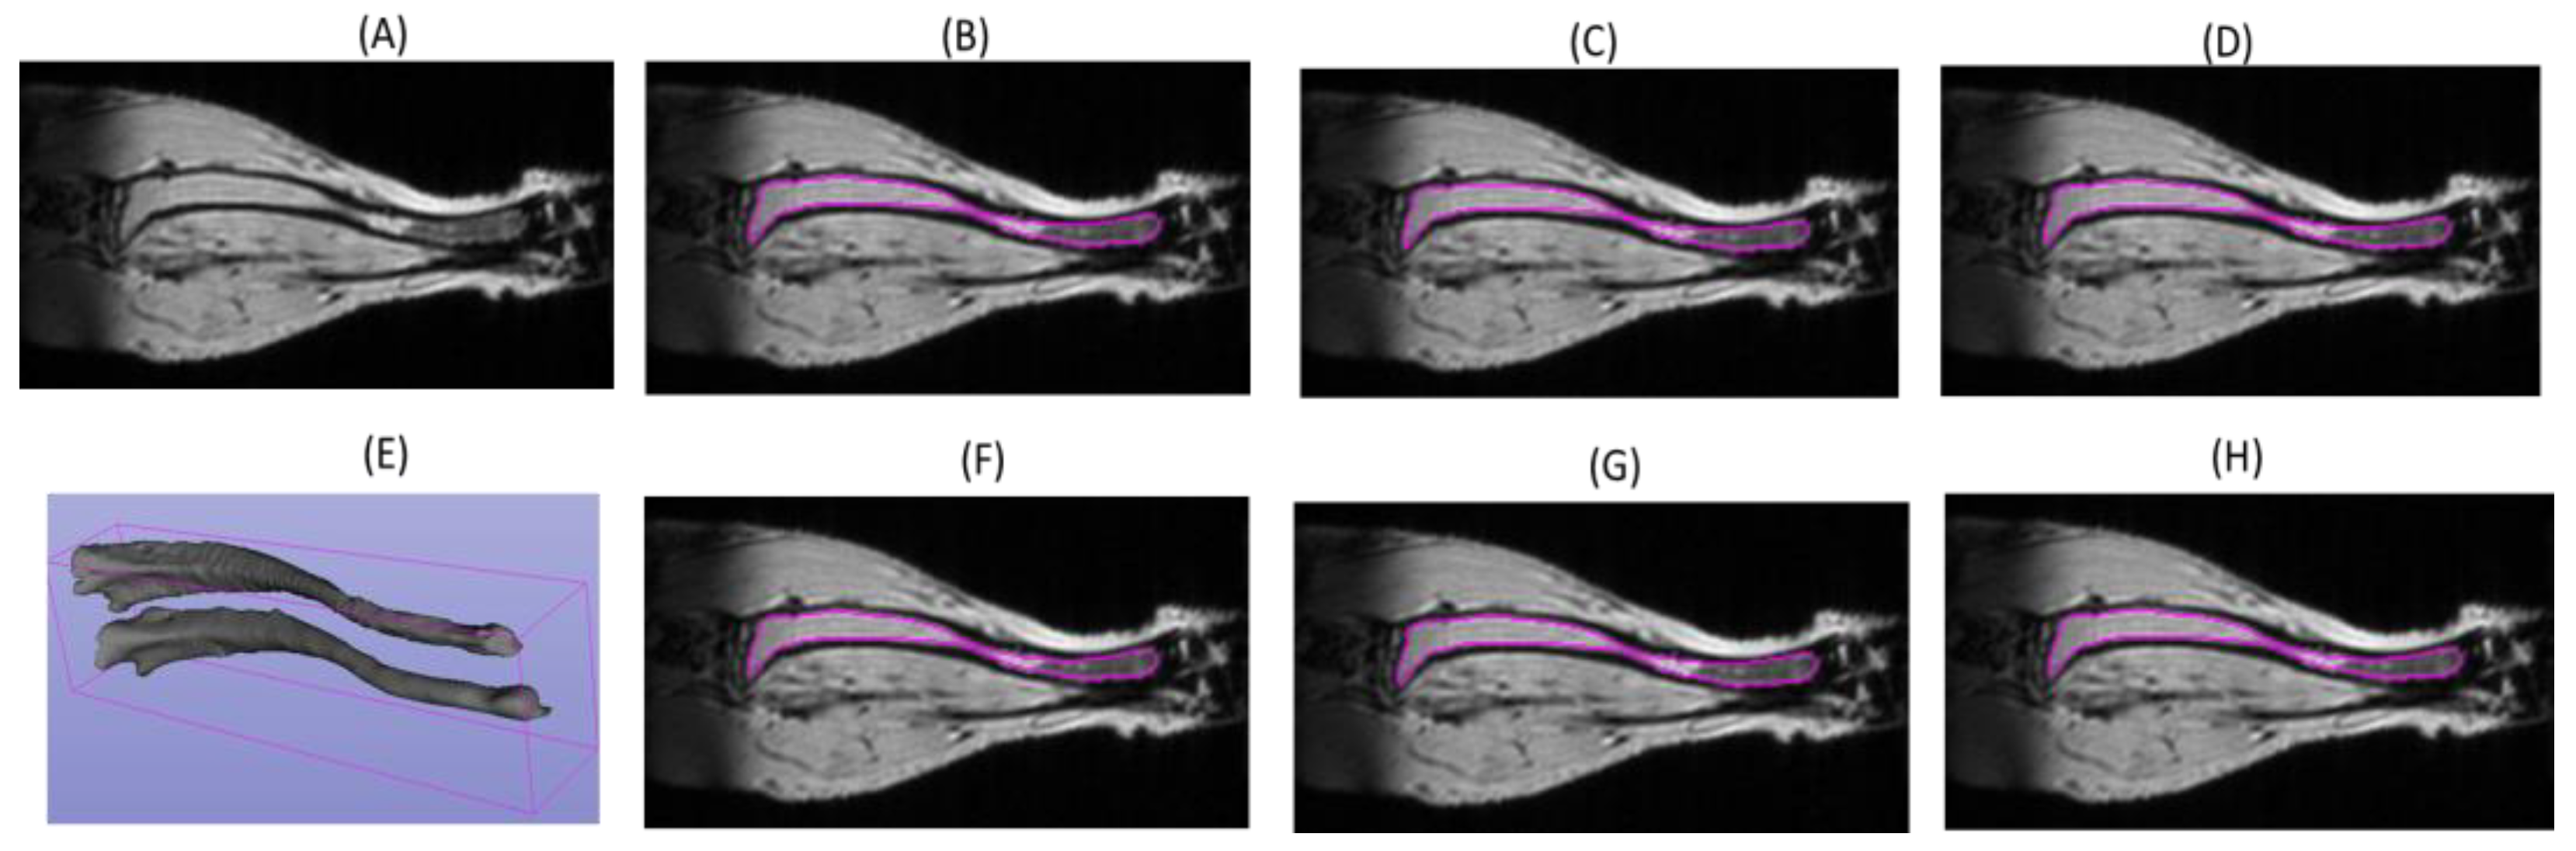

An example of the tibia segmentation from the validation set is presented in Figure 3. A darker tibia bone boundary is clearly visible. All the models accurately predicted the tibia bone contour with very minimal variations from the expert annotations even in regions of signal heterogeneity along the tibia length (Figure 3). The change in the tibia volumes over a period of 6 weeks (Figure 3E) was consistent with minor changes in the contours.

Figure 3.

Examples of mouse tibia segmentation contours (magenta) for a single-slice MRI image in the test set (A) delineated by expert annotators ((B) EA1; (F): EA2) and by DL model with different training scenarios; (C) full training subset; (D) TS1; (G) TSM; (H) TS2). (E) The full tibia 3D volume segmentation by EA1 for two scans (6 weeks apart) of the same mouse (top = 6.5 mm3; lower = 9.9 mm3).

In the test example shown in Figure 4, the DL model segmentations derived after training with full and half datasets (Figure 1, TS1 and TS2) apparently produced slightly more accurate tibia segmentation at the distal end compared to somewhat under-segmented EA1 “reference” (Figure 4B, yellow arrow). Since expert segmentation may have variabilities, the agreement or disagreement with respect to the reference annotations may not reflect the true model accuracy (Table 1). The predictions made by all the models (Attention U-Net trained on multiple mice) are fairly robust except for the one trained on a single mouse (Figure 4G). The predicted tibia mask by the model trained on the TSM subset misses a large portion of bone contour near the knee (indicated by the yellow arrow in Figure 4G). Thus, the model learned from a small training set shows declining performance and is more susceptible to errors in reference annotations of the training samples. The small data size fails to include all the diversity and features that would be encountered while making the test predictions.

Figure 4.

Examples of mouse tibia segmentation contours (magenta) for a single-slice MRI image in the test set (A) delineated by expert annotators ((B) EA1; (F) EA2) and by DL model with different training scenarios (C) full training; (D) TS1; (G) TSM; (H) TS2). (E) The full tibia 3D volume (6.5 mm3) segmentation by EA1. The yellow arrows indicate apparent tibia under-segmentations in (B) and (G).